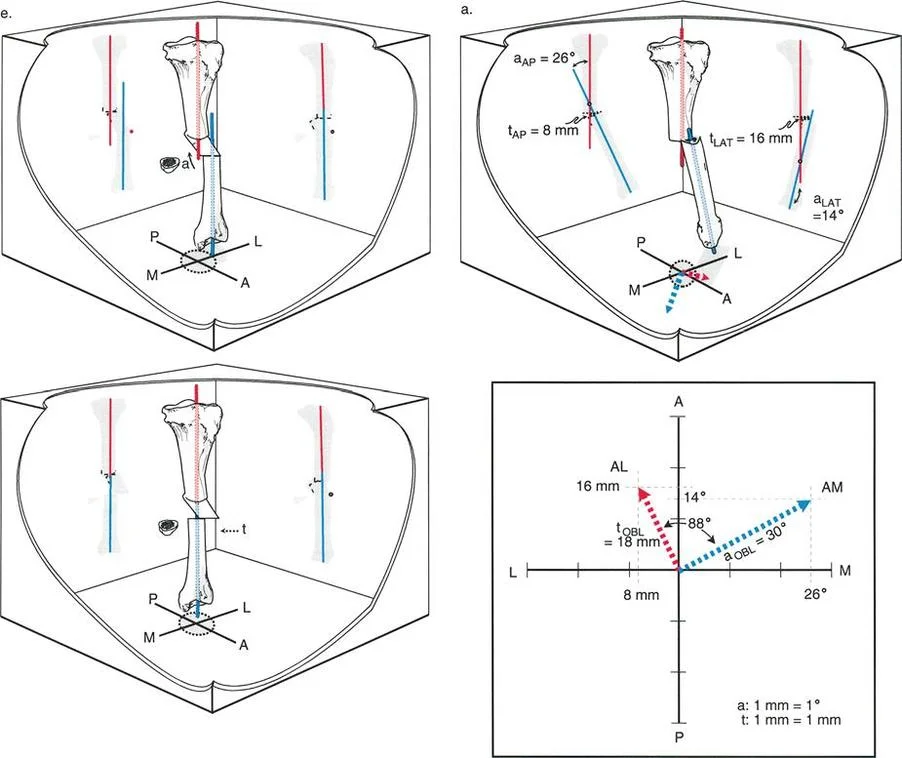

Standard orthogonal radiographs (anteroposterior and lateral) of the affected extremity are mandatory. Radiographs help delineate the extent of bone involvement, identify protruding phalangeal shafts in intrauterine amputations, and reveal characteristic bony deformities caused by the chronic constriction.